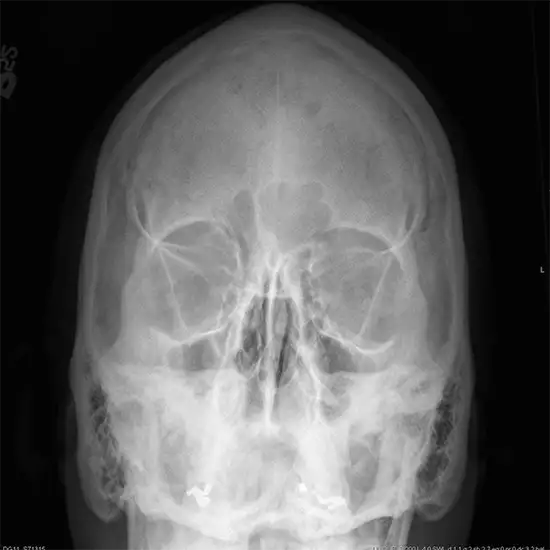

The Caldwell view is meant to show the frontal sinus more clearly than a skull radiograph and is obtained with a PA beam, with 15 degrees of caudal angulation. X-Ray Skull Caldwell view is also known as X-ray Skull occipital frontal projection

This view is useful in assessing:

• Frontal sinuses

• Ethmoid sinuses

• Sinus polyps

• Orbital fracture

• Paranasal sinuses

• Facial fracture